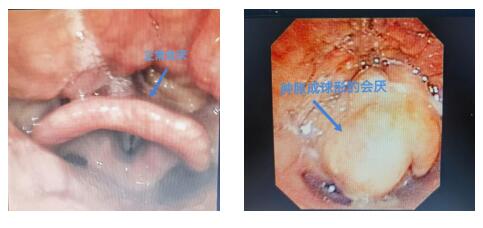

什么是急性会厌炎?

急性会厌炎是一种严重的喉部疾病,通常由细菌感染引起,发病急骤且进展迅速。会厌是位于咽喉部位的一块软骨组织,当它发生炎症时会导致喉头水肿,进而引发呼吸困难甚至窒息。